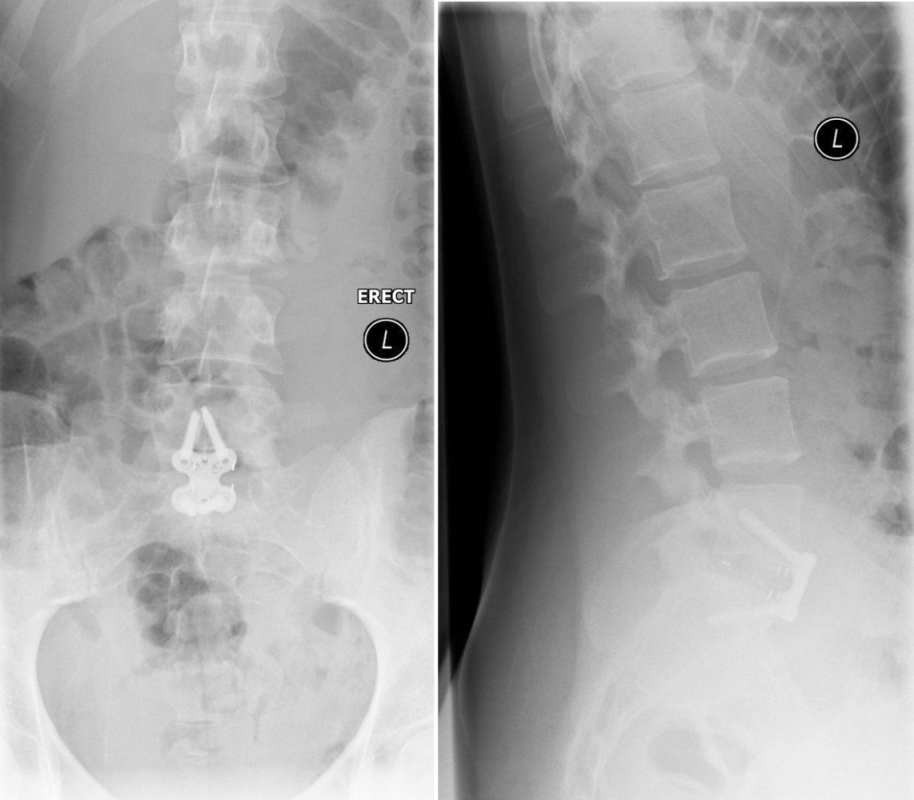

A 19-year-old high-level college hockey player had experienced 12 months of severe lower back pain (LBP), and was unable to play sport due to high disability and pain (Fig 9). Nonoperative treatment with physiotherapy and injections had failed.

The CT showed bilateral L5 spondylolysis with grade I spondylolisthesis (Fig 10).

The patient underwent minimal access L5/S1 anterior interbody fusion with BMP followed by minimally invasive Matrix percutanous screw fixation (Fig 11).